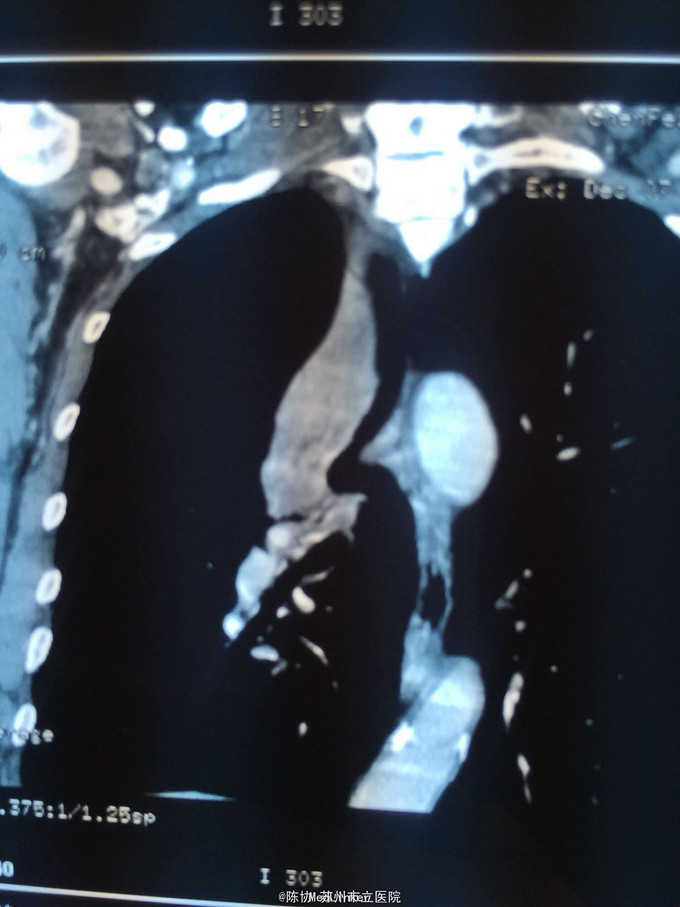

主诉:体检发现右上肺不张半月 77岁男,半月前体检发现右上肺不张,无不适。无消瘦,无咳血,无干咳。去年4月右上肺炎,抗生素治愈,当时CT未见肺肿块。入院支气管镜发现右上支气管开口组织增厚闭塞,开口近侧有隆起约3x3平方毫米,取活检5块病理示中度非典型增生。CT提示在右侧主支气管外侧有30x30平方毫米块影,压迫右上支气管开口处。三大常规和生化检查正常,肿瘤指标正常,TAP正常。

右侧中央型肺癌 重做支气管镜,精于定位找到病症组织,获得病理诊断来指导治疗。 胸外科医生不建议手术,理由是肿瘤位置靠近主支气管和气管,袖状切除不一定看干净。 请问正确的诊断,和比较合理的治疗方法是什么?求助大家思考评论